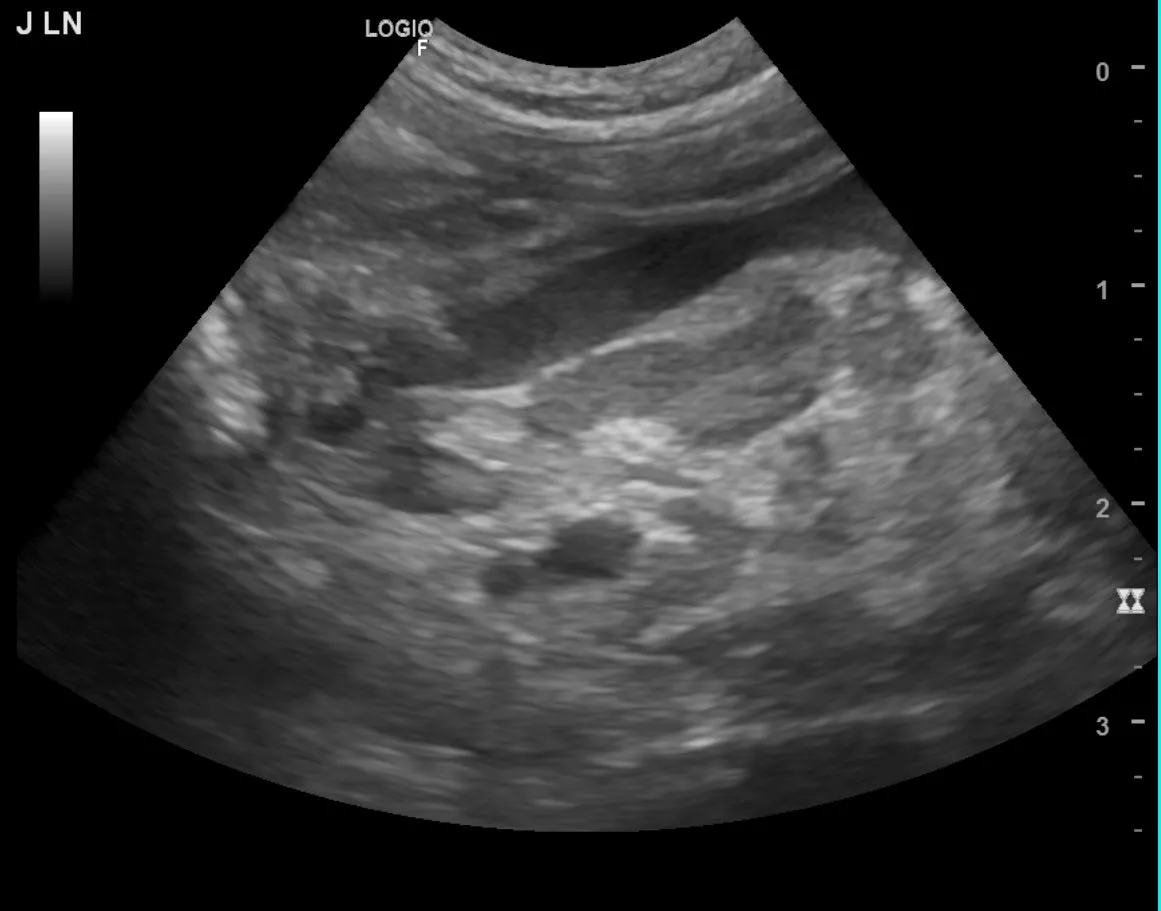

兩歲英短貓 Kiki 在健康檢查中被發現腹部淋巴結腫大、形成明顯腫塊,原診所懷疑是淋巴瘤,建議轉診至本院評估,準備化療。😰

但我們仔細評估後,發現牠不屬於好發年齡與品種,並進一步檢查發現:

一歲的 Mimi 到院時精神不佳、貧血,超音波發現空腸周邊淋巴結腫大、合併少量腹水,看起來像腫瘤或 FIP。

兩歲英短貓 Kiki 在健康檢查中被發現腹部淋巴結腫大、形成明顯腫塊,原診所懷疑是淋巴瘤,建議轉診至本院評估,準備化療。😰

但我們仔細評估後,發現牠不屬於好發年齡與品種,並進一步檢查發現:

一歲的 Mimi 到院時精神不佳、貧血,超音波發現空腸周邊淋巴結腫大、合併少量腹水,看起來像腫瘤或 FIP。